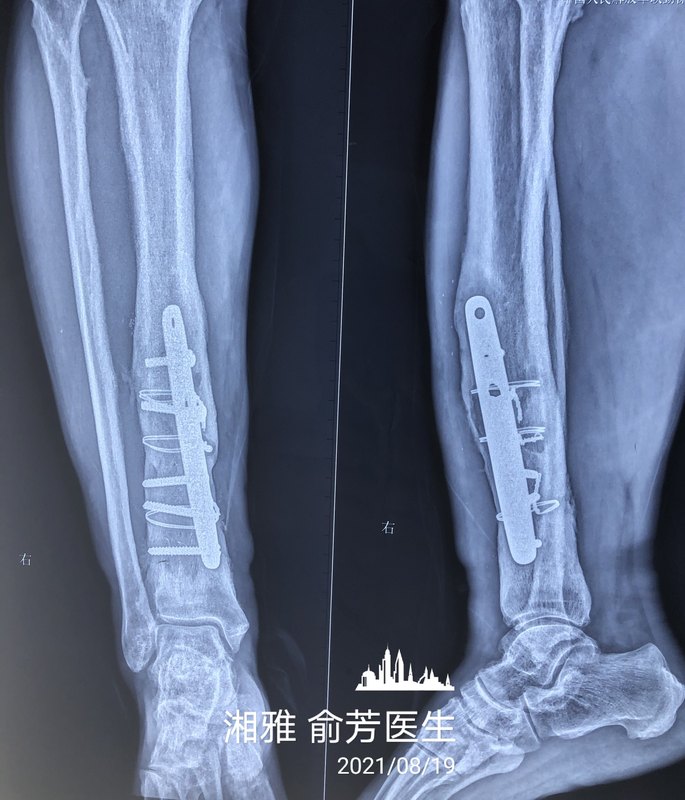

陳大叔在二十多年前受的傷,上了脛腓骨的鋼板,以為骨折處理好了就沒事了,過了段時(shí)間發(fā)現(xiàn)傷口流膿,一流就流了二十多年,痛苦不已。 我們首先把脛腓骨的鋼板和鋼絲取了,里面有很多膿,脛骨骨皮質(zhì)感染壞死一半,皮膚也缺損很多。 清了兩次創(chuàng)后,里面的壞死、感染組織基本上被清除干凈了,我們就設(shè)計(jì)用腓動脈嵌合穿支皮瓣修復(fù),腓骨瓣重建脛骨,皮瓣覆蓋創(chuàng)面。 手術(shù)很順利,帶了三個穿支,皮瓣通血也很好。 陳大叔二十多年的骨髓炎老問題終于解決了。